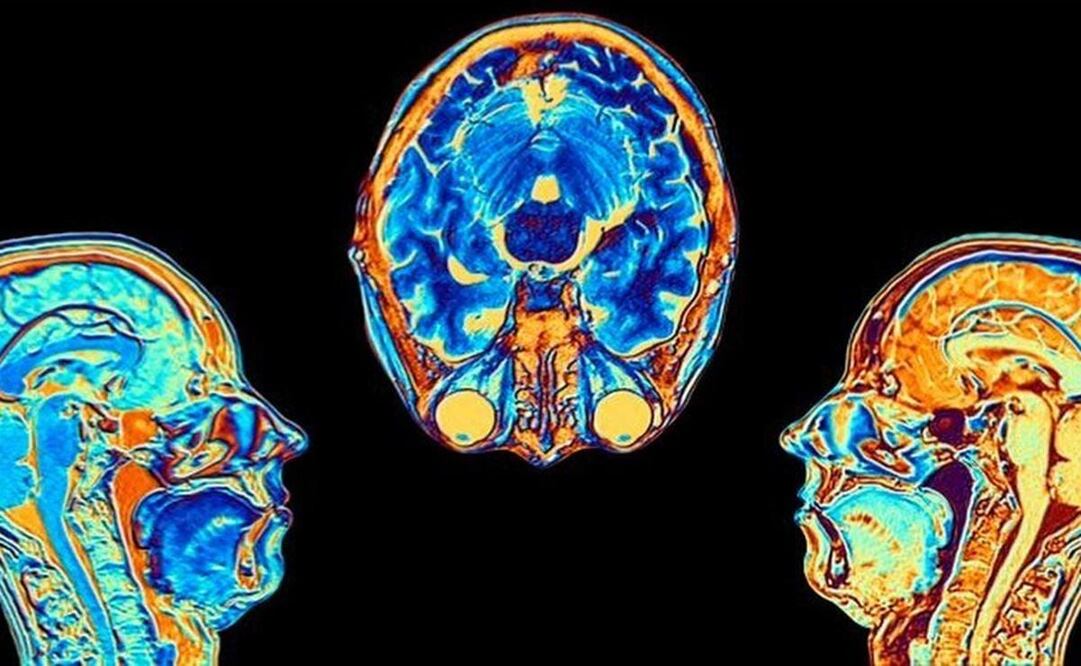

Contagiarse de Covid-19 puede provocar cambios en el cerebro, según indicó un estudio publicado en la revista "Nature" y en este Día Mundial del Cerebro 2022 vale la pena abordarlo.

Los investigadores hallaron diferencias significativas en las resonancias magnéticas hechas antes y después de la infección.

Incluso después de una infección leve, las imágenes mostraron que el tamaño total del cerebro se había reducido ligeramente, con menos materia gris en las regiones relacionadas con el olfato y la memoria.